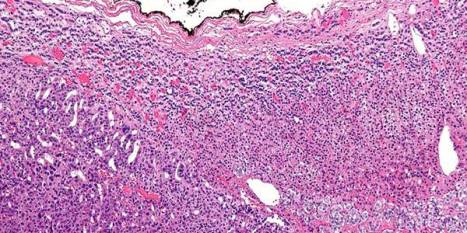

Corticotropin-independent macronodular adrenal hyperplasia may be an incidental finding or it may be identified during evaluation for Cushing’s syndrome. Reports of familial cases and the involvement of both adrenal glands suggest a genetic origin of this condition.

The most frequent somatic chromosome alteration was loss of heterozygosity at 16p (in 8 of 33 patients for whom data were available [24%]). The most frequent mutation identified by means of whole-genome sequencing was in ARMC5, located at 16p11.2. ARMC5 mutations were detected in tumors obtained from 18 of 33 patients (55%). In all cases, both alleles of ARMC5 carried mutations: one germline and the other somatic. In 4 patients with a germline ARMC5 mutation, different nodules from the affected adrenals harbored different secondary ARMC5 alterations. Transcriptome-based classification of corticotropin-independent macronodular adrenal hyperplasia indicated that ARMC5 mutations influenced gene expression, since all cases with mutations clustered together. ARMC5 inactivation decreased steroidogenesis in vitro, and its overexpression altered cell survival.

Some cases of corticotropin-independent macronodular adrenal hyperplasia appear to be genetic, most often with inactivating mutations of ARMC5, a putative tumor-suppressor gene. Genetic testing for this condition, which often has a long and insidious prediagnostic course, might result in earlier identification and better management. (Funded by Agence Nationale de la Recherche and others.)